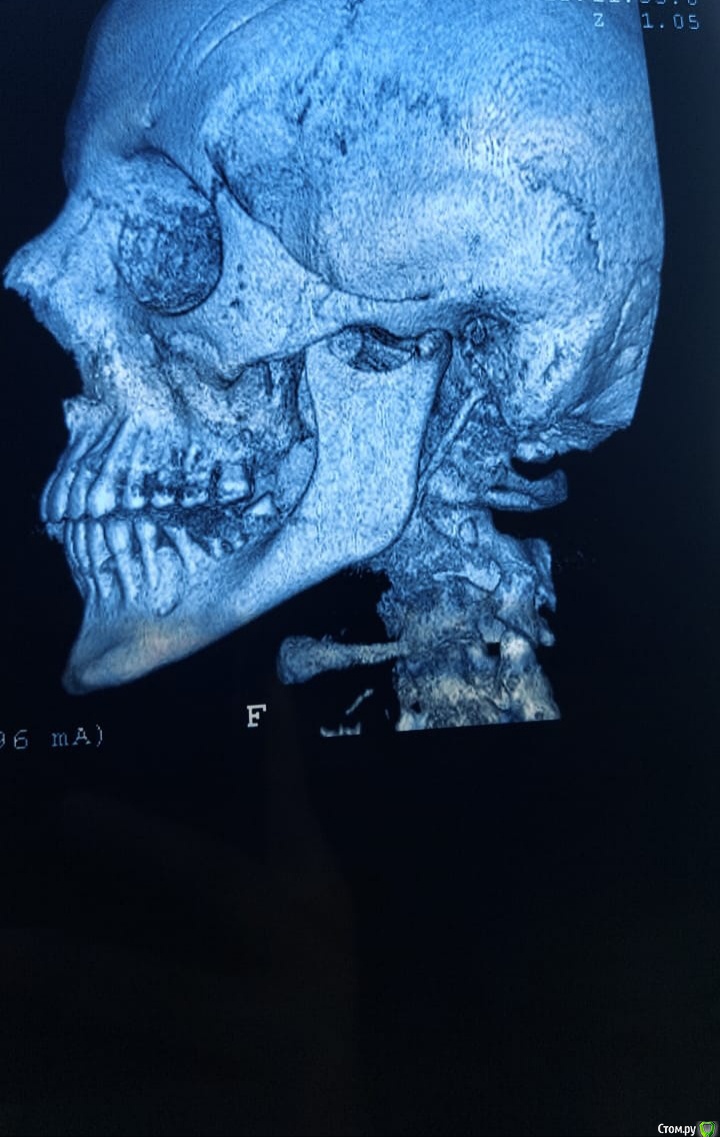

Kainat Опубликовано 22 августа, 2020 Поделиться Опубликовано 22 августа, 2020 Здравствуйте, уважаемые форумчане!У пациентки перелом скуловой кости. Жалобы на ограничение открывания рта, онемение подглазничной области. Была проведена репозиция по Лимбергу. После репозиции немножечко улучшилось открывание рта. Прошел месяц, деформации не наблюдается, однако у пациентки пока сохраняется онемение, в щечной области правда восстановилась чувствительность. Основная жалоба на ограничение открывания рта (2пальца). Может ли это быть связана с мышечной контрактурой, т.к. отек мягких тканей был очень сильным и до сих пор полностью не прошел. Данные кт прилагаются (первые три рисунка до репозиции). Благодарю заранее! Ссылка на комментарий

Irouil Опубликовано 23 августа, 2020 Поделиться Опубликовано 23 августа, 2020 Вы видите причину ограничения открывания рта? Могу выслать видео кт...Не вижу, просто без структурных причин месяц контрактуры я не встречал. Можете выложить просто на файлообменник В смысле деформации костной ткани не наблюдается, симптом ,,ступеньки" не наблюдается...Теперь ясно. По предоставленным срезам репозиция успешная. Может гематома инкапсулированная где-то, гемосинус был Ссылка на комментарий